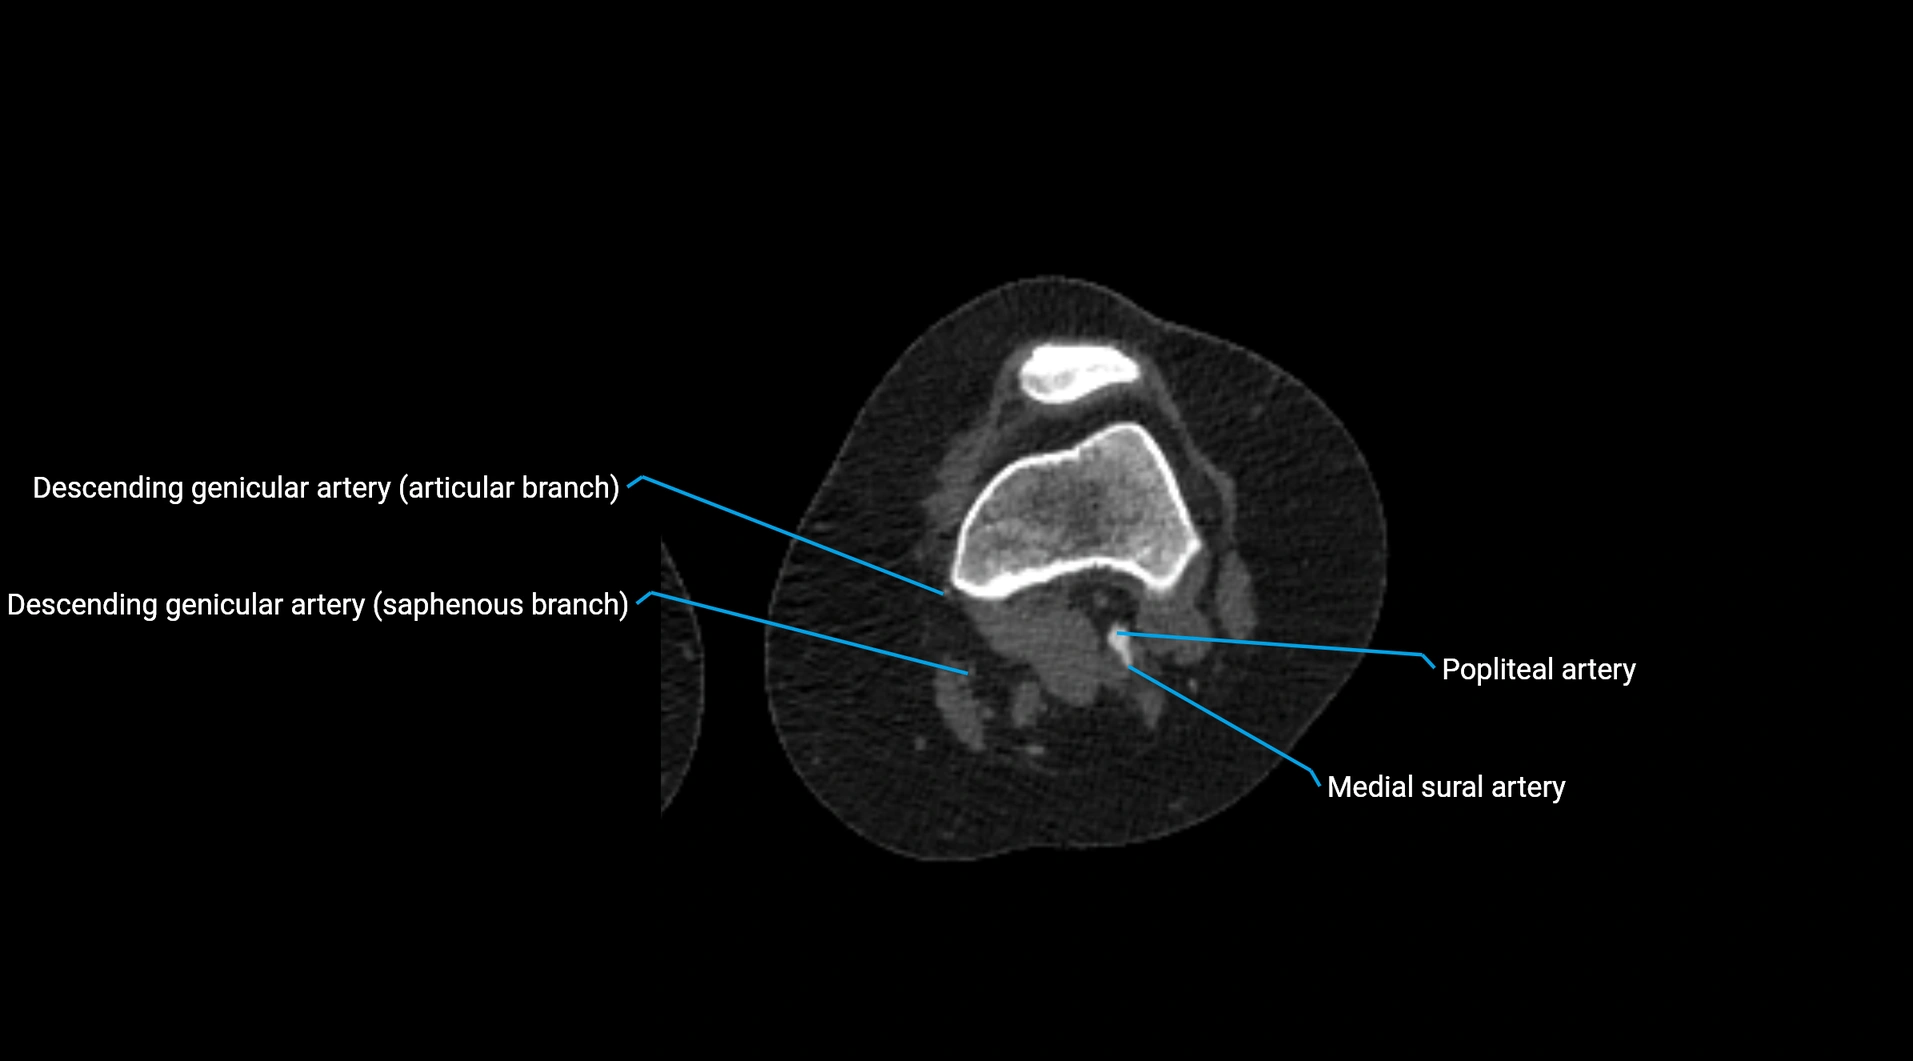

CT Appearance

Non-contrast CT:

• Appears as a tubular soft tissue structure anterior to vertebral bodies

• Calcified atherosclerotic plaques appear as hyperdense foci along the wall

• Useful for screening abdominal aortic aneurysm (AAA) size and mural calcification

Contrast-enhanced CT (CTA):

• Gold standard for abdominal aortic imaging

• Provides excellent detail of lumen, wall, aneurysm, thrombus, and branch vessels

• Multiplanar and 3D reconstructions help in aneurysm measurement, stent graft planning, and dissection evaluation

• Detects acute rupture, traumatic injury, or occlusion with high sensitivity